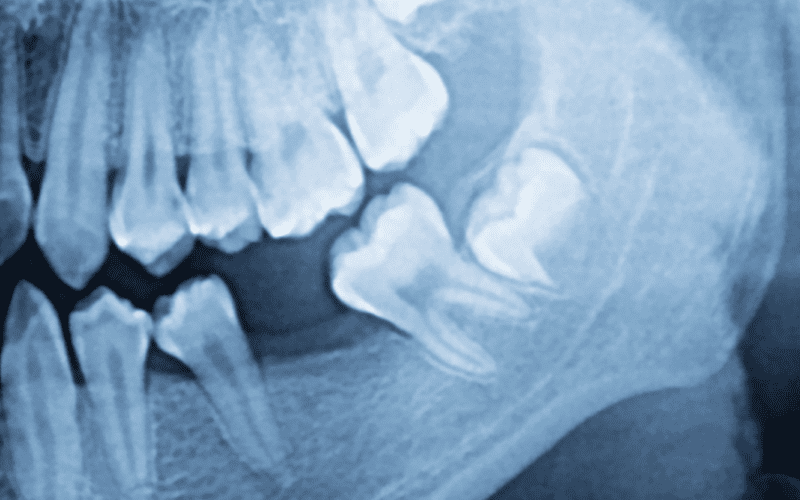

How Early Can Wisdom Teeth Be Seen on a Dental X-Ray?

Dental X-rays may reveal wisdom teeth growth at 10-12 years old. A panoramic X-ray may show wisdom tooth buds at this time.

Dentists use X-rays to inspect wisdom teeth. These scans measure tooth size, location, and angle before erupting. Dental professionals may anticipate wisdom tooth growth using panoramic or periapical X-rays. Detecting issues early allows for proactive treatment and eruption planning. This helps identify how to know if your wisdom teeth are coming in or when do your wisdom teeth come in.